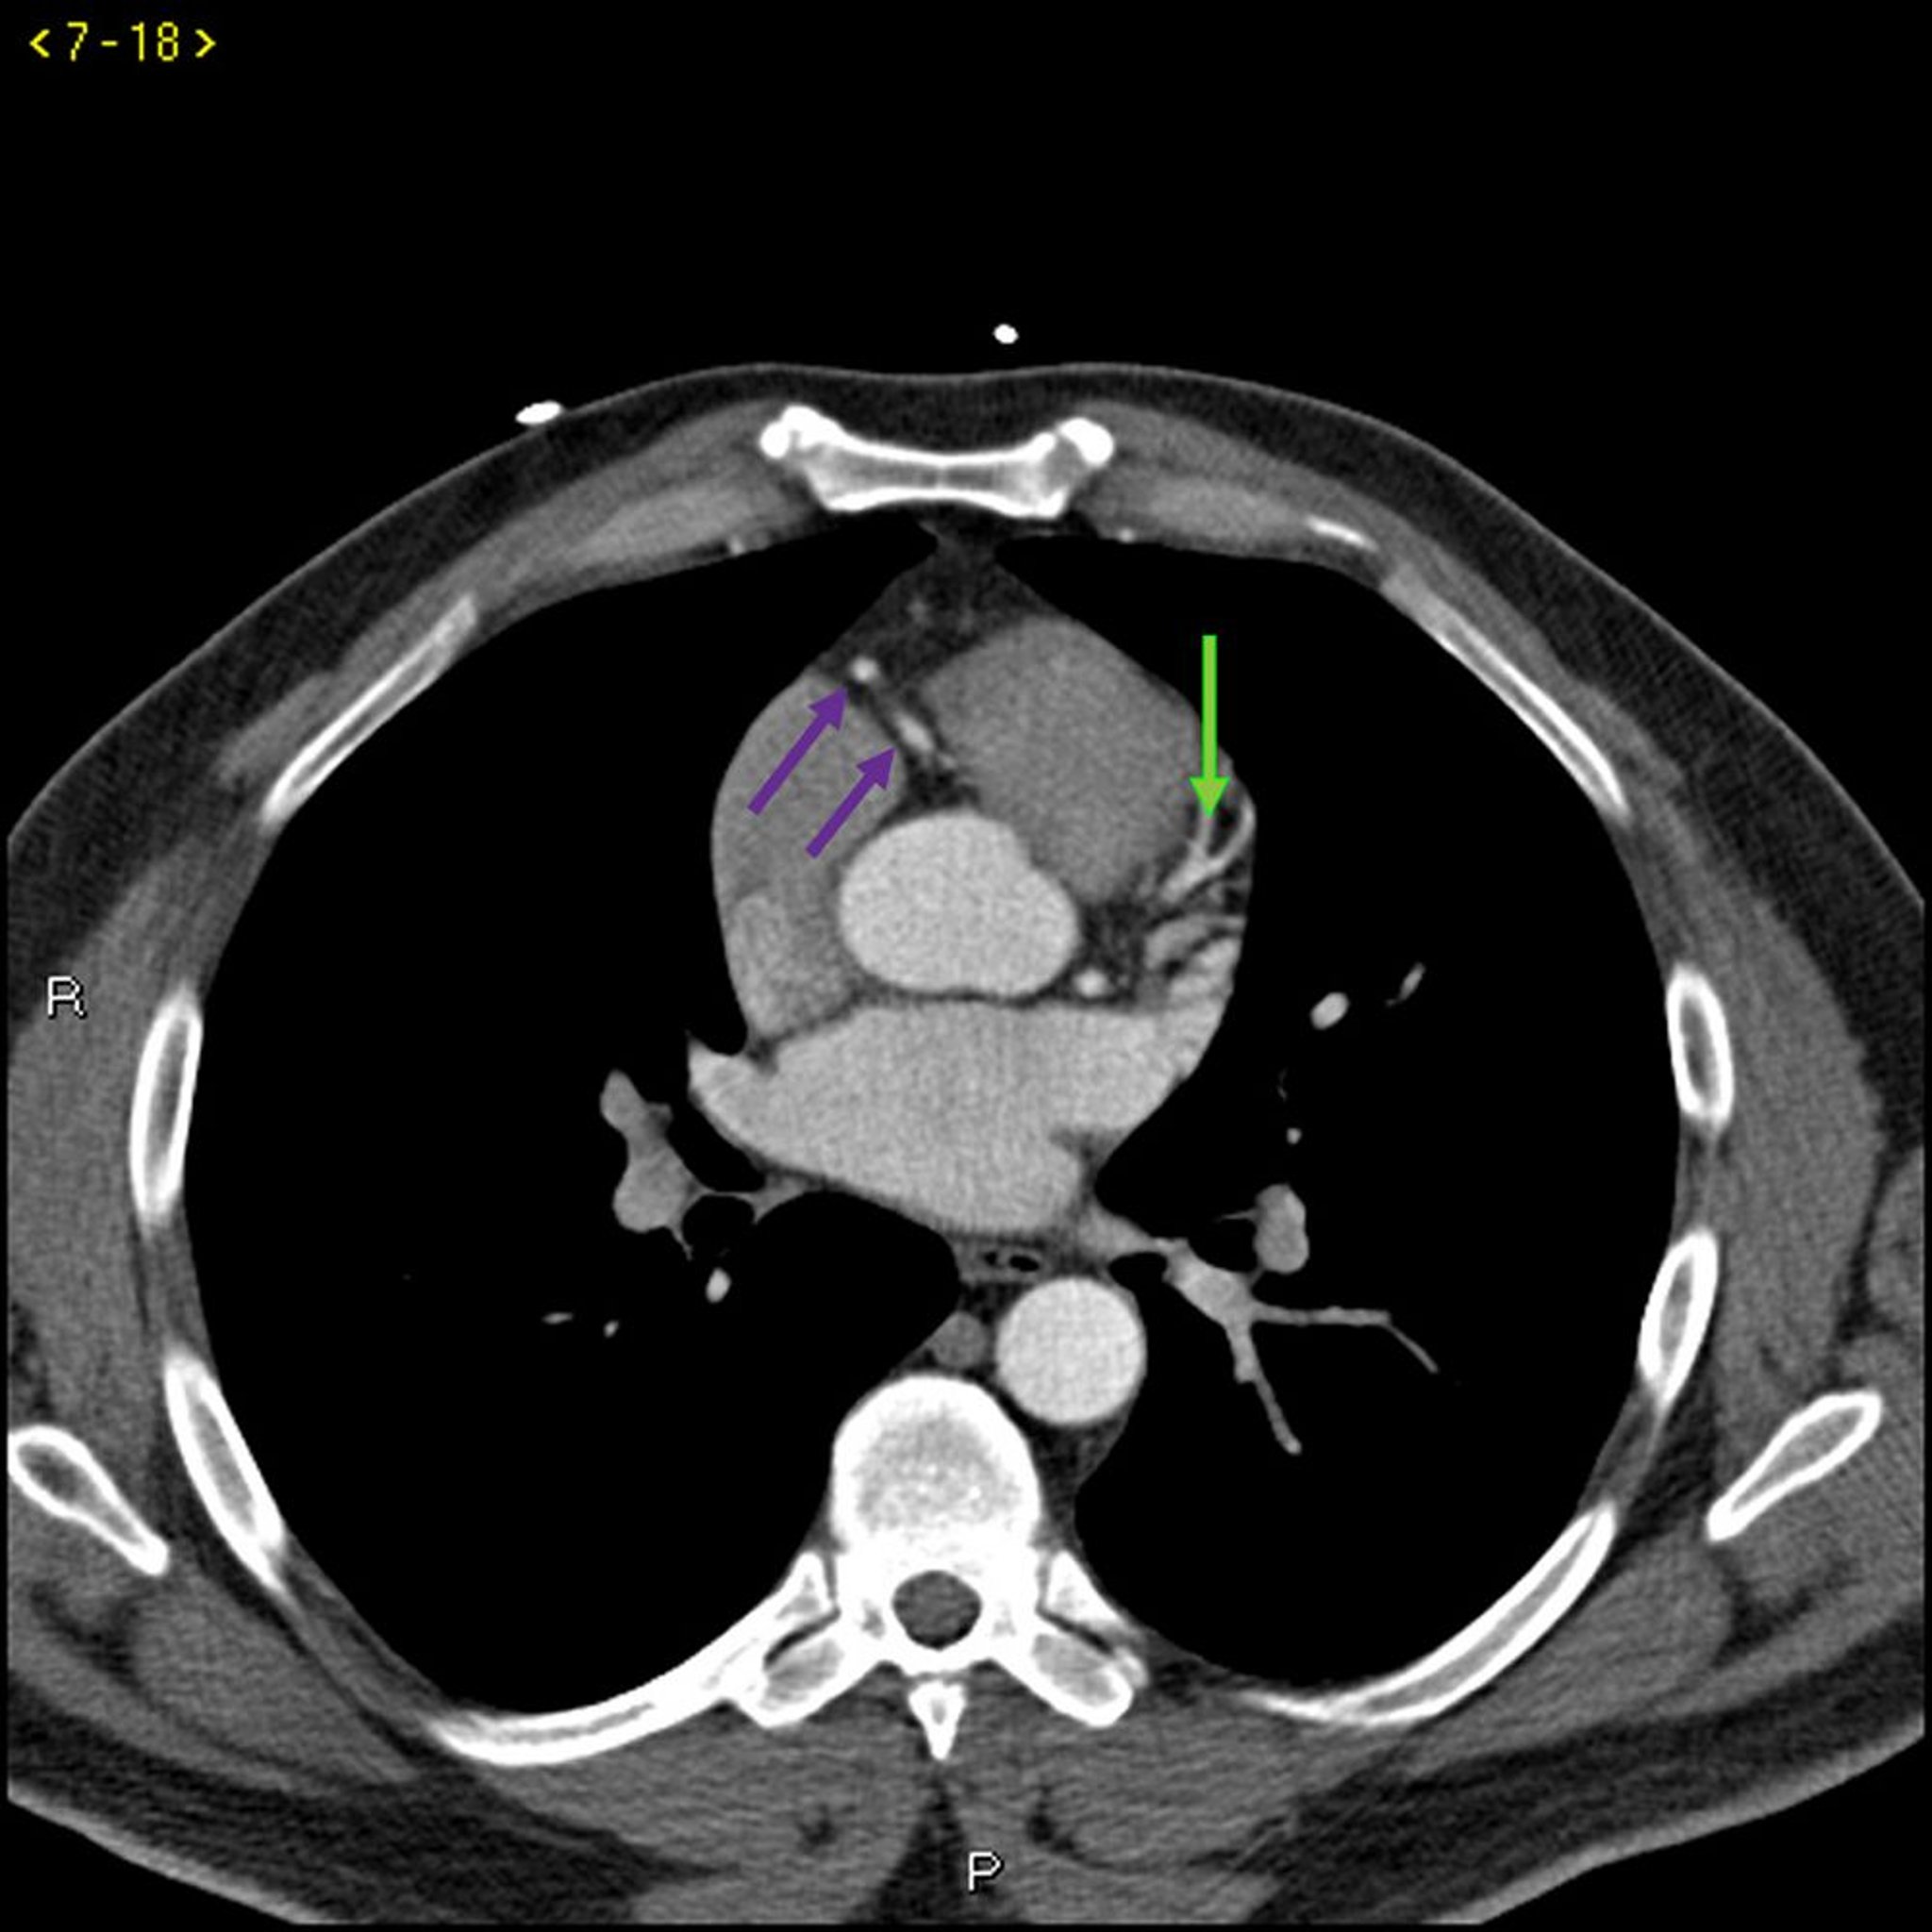

この造影CTには正常な冠動脈が写っている。左主幹部が赤矢印で示されている。左前下行枝および左回旋枝がそれぞれ緑矢印および青矢印で,右冠動脈が紫矢印で示されている。